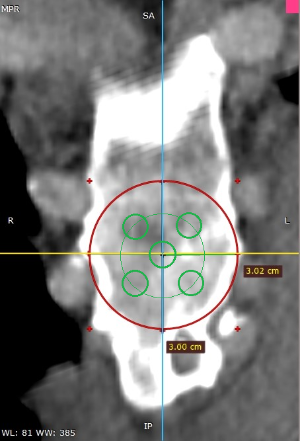

Les dades mèdiques del pacient, més l'exploració clínica realitzada per l'equip de cirurgia, juntament amb una anàlisi detallada de les imatges del TAC i les reconstruccions digitals en 3D de cada tòrax realitzades conjuntament amb l'equip d'enginyers de Ventura Medical Technologies, són la base per determinar si la tècnica Pectus Up està indicada i com cal procedir en cadascun dels pacients.

Amb aquestes dades se selecciona l'implant que millor s'ajusta a l'anatomia de cada tòrax, la ubicació exacta del sistema d'elevació i, alhora, proporciona a l'equip quirúrgic un detall dels passos que cal tenir en compte per fer-ne una correcta implantació.

Pectus Excavatum Pectus Excavatum Asimétrico Índice de Asimetría 0.6 (+R/-L)(|AI|> 0.05 Asimétrico) Índice de Haller 4.5 (HI >3.5) Índice de Corrección 49.13% Rotación esternal 18.1 ° (a la derecha)

Informe d'avaluació del TAC d'un pacient enviada al cirurgià